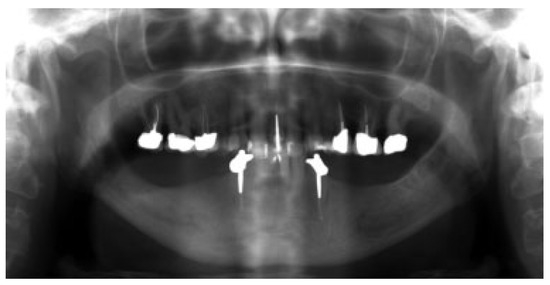

In 15 patients, 14 ablative surgical interventions were recorded, with 14 receiving primary or secondary reconstructive procedures; in one patient, no reconstructive procedure was performed due to a compounding medical condition (Table 2). This patient was excluded from further analysis due to lack of reconstruction. Eight patients had primary head and neck cancer, but in only four patients the condyle was involved due to infiltration, while four suffered from ORN. One patient suffered from a rare benign tenosynovial giant cell tumor. Two patients suffered from extensive osteomyelitis, and bisphosphonate osteonecrosis afflicted two patients. One patient had to be operated on twice due to hypertrophic bone formation around the metal condylar head and represents the only major complication in our series. She suffered facial nerve damage during the second surgery in a postradiated field, with the facial nerve lying on the reconstruction plate used in the first surgery (Figure 1). Six of the fourteen reconstruction surgeries took place in a radiated field, explaining the two plate exposures in an unrelated area, away from the condylar reconstruction. Two patients received total joint reconstructions combined with one and in the other two free flaps. Five patients received fibula flaps alone and one received a vascularized costochondral graft, while all of the others had metal condylar prostheses with or without a free flap (Figure 2, Figure 3 and Figure 4). Follow-up ranged from 2 to 84 months with an average of 30 months. In total, five patients suffered from complications that could be considered acceptable, as they all could be corrected with minor revision surgery or occlusal adjustment. One patient suffered from facial nerve damage after a reconstruction plate in which metal condyle had to be removed in a radiate. In 11 patients, reliable information was obtained regarding mouth opening of which 9 showed a marked improvement of more than 5 mm. Three patients had a decrease in mouth opening, but all could be regarded as functional as no mouth opening of less than 30 mm was recorded (Figure 4).

Figure 1.

Hypertrophic bone around metal condylar replacement.